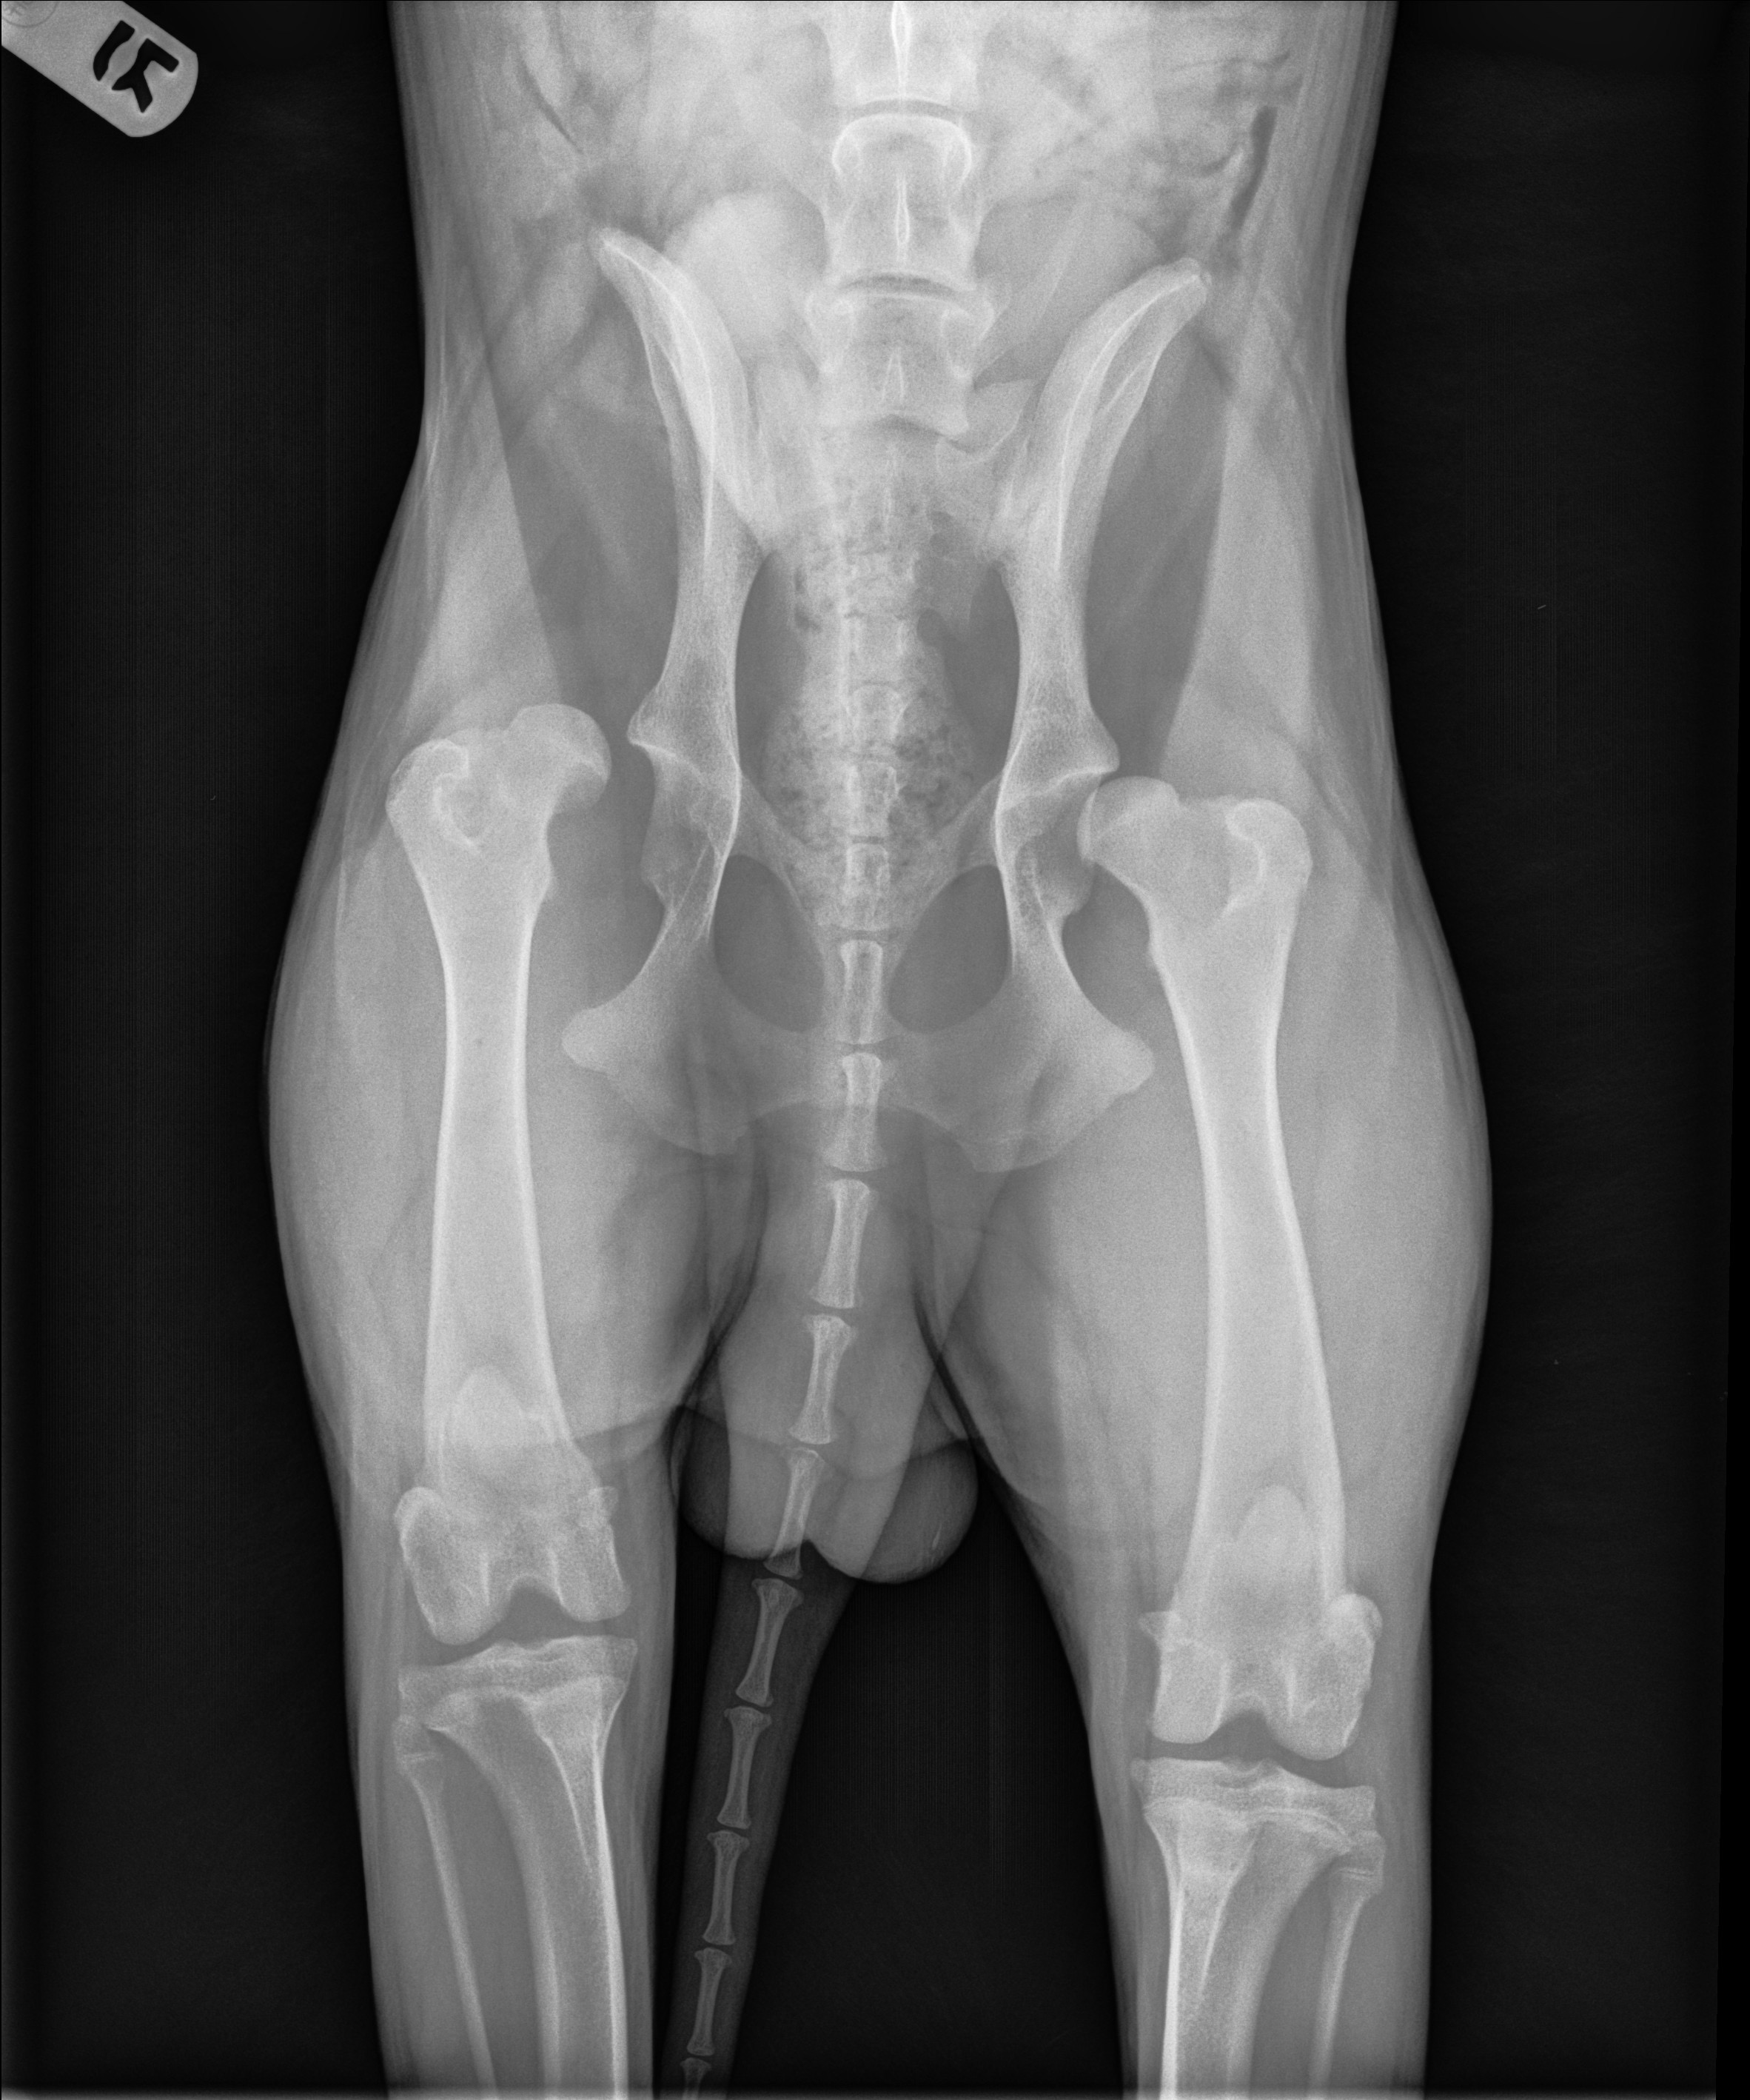

Hello everyone! This is my first time ever making a gofundme and it’s for my special boy Kuma. He had to have an FHO surgery back in November 2024 due to, what I assume, was from his sister going down the stairs too fast behind him and might have ran into him. Took him in when I noticed the slight limp and they saw that his femur was dislocated from the hip and I believe they told me that it might’ve been fractured as well. Luckily I was able to use CareCredit to pay for the surgery to be done within a few days, I didn’t want him to walk on that any longer. He has healed up really well, he has a bit of an irregular gait but that’s alright as long as he isn’t in pain.